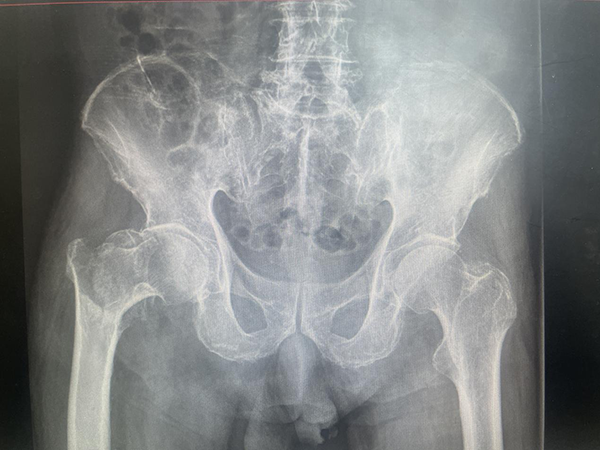

89歲的陳大爺在家中不慎摔倒,右側(cè)髖部著地后無(wú)法站立。于當(dāng)?shù)鼐驮\行X線檢查后診斷為“髖部骨折(股骨粗隆間骨折)”。髖部骨折又被稱為“人生的最后一次骨折”。75歲以上老人如遭遇髖部骨折,生活將難以自理,大部分需要長(zhǎng)期臥床,極易導(dǎo)致褥瘡、肺炎和血栓的發(fā)生,嚴(yán)重可危及生命。因此,髖部骨折建議首選手術(shù)治療。陳大爺經(jīng)兩月保守治療無(wú)果后,為尋求站起來(lái)的可能,來(lái)到徐州市中醫(yī)院骨科就診。如何為陳大爺選擇一個(gè)合適的手術(shù)方案顯得尤為重要。89歲高齡,臥床保守治療期間出現(xiàn)肺部感染及深靜脈血栓等并發(fā)癥,既往有房顫、肺栓塞等病史,此次髖部骨折對(duì)陳大爺來(lái)說(shuō)意味著直面死亡。即便高齡,但陳大爺思維清晰,下地行走活動(dòng)欲望強(qiáng)烈,經(jīng)過(guò)溝通后堅(jiān)持要求給予手術(shù)治療。

●(術(shù)前X線片)